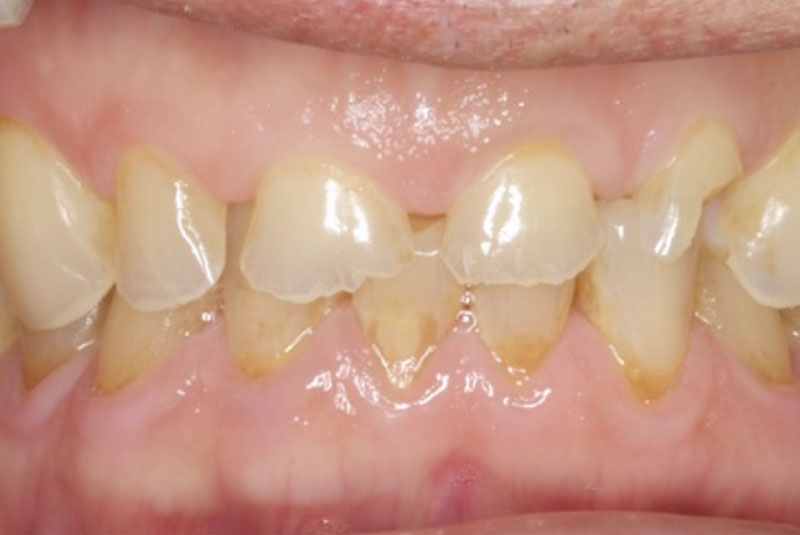

Before & After Crowns (#6,7,8,9,10,11,22,23,24,25,26,27), Overlay (#3,4,13,14,21,28,29), Implant & Implant Crowns (#5,12,19,20,30)